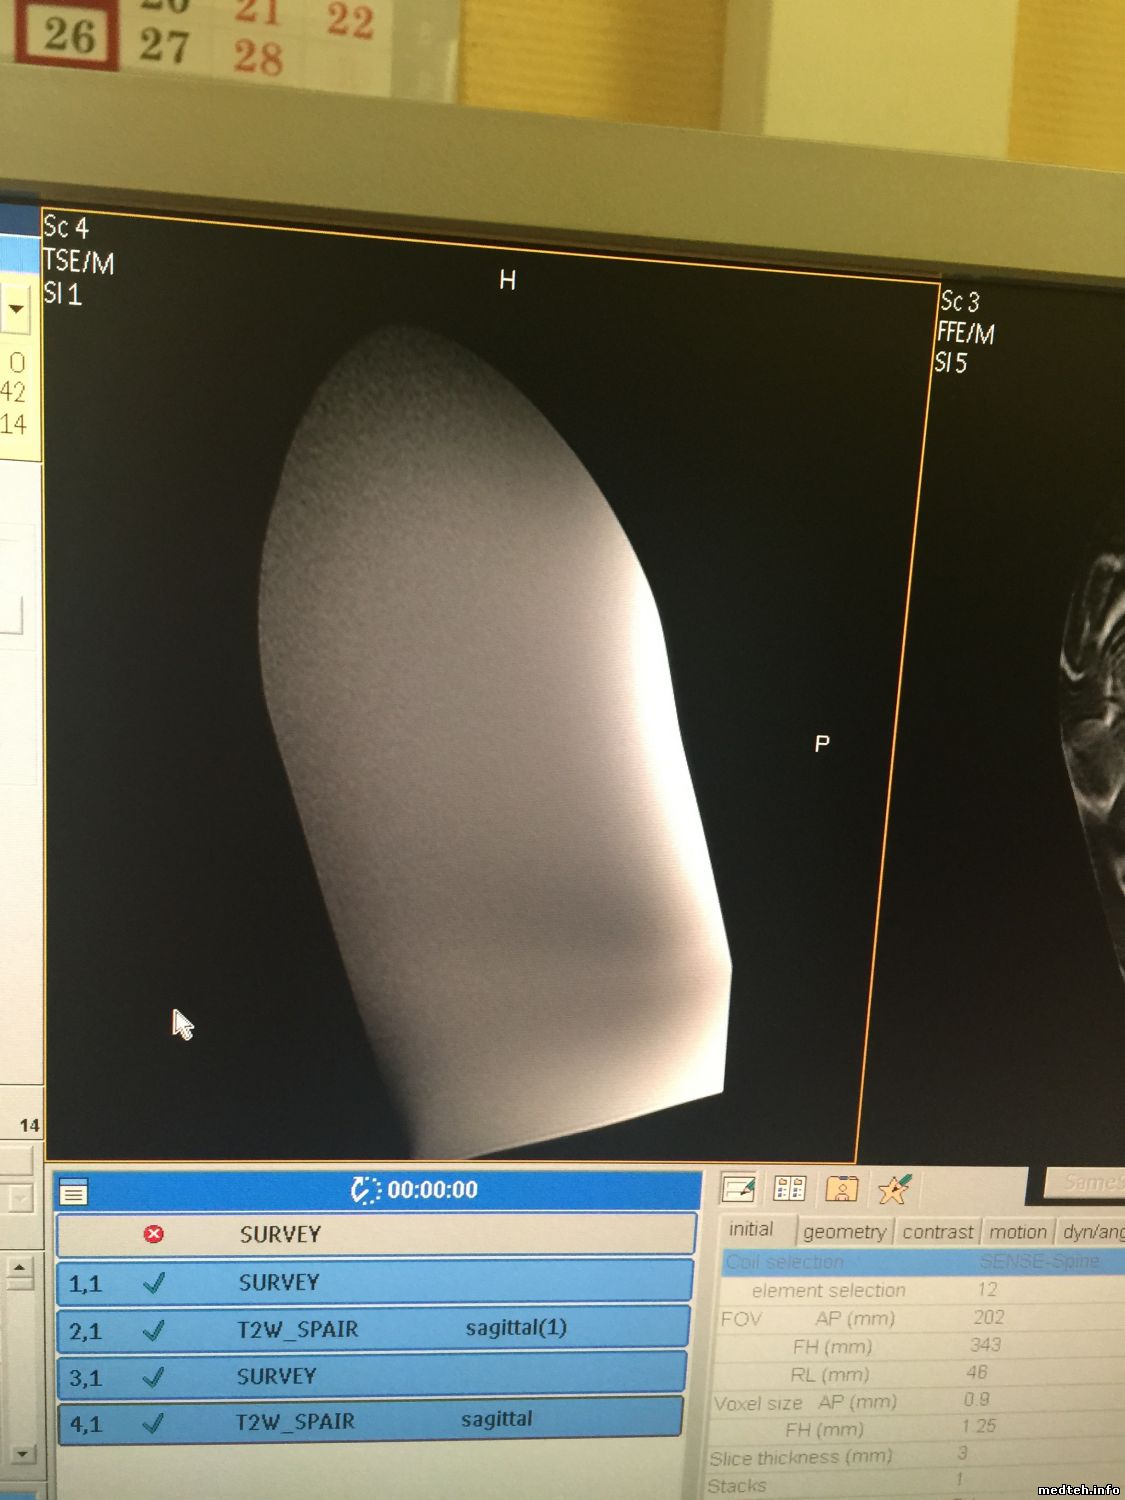

Привет всем, кто знает подскажите пожалуйста! Борюсь с магнитом Philips Achieva не первый день, сделав все возможные настройки и калибровки, пришел к такому результату ( см. фото) артефакт неоднородности, более заметен на протоколах подавления жира. Думаю проблема либо в одном из градиентов либо поле убежало, как правильно отбраковать настраивать ( 781 ) градиенты и где на этих моделях протягиватъ контакты.

2539895.jpg (106.9 Kb) · 0635526.jpg (108.4 Kb) · 1862152.png (603.8 Kb) · 3915910.png (594.0 Kb) · 9915248.png (599.3 Kb)